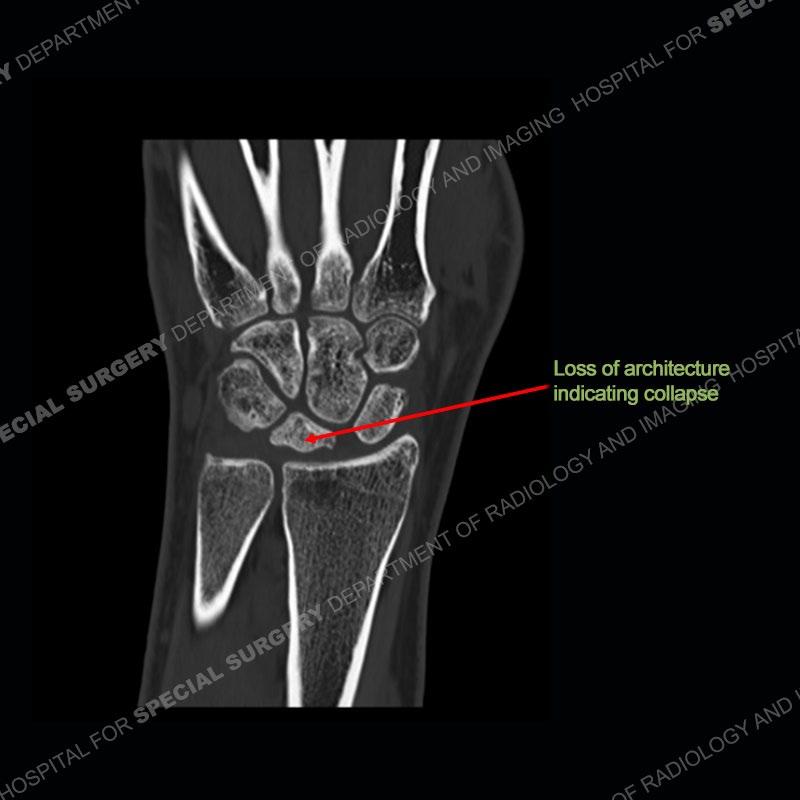

Both cases demonstrate similar findings to slightly less and more conspicuous degrees. The radiographs show sclerosis and fragmentation/collapse of the lunate. The CT images for case one just further clarify the architecture of the lunate. The MRI images show a slightly greater degree of variability but with overall persistent areas of low signal of the lunate on all pulse sequences and with a loss of the geometry of the lunate indicating collapse and fragmentation.

A well recognized but still poorly understood entity with necrosis and collapse representing the end stage of the pathology. The reasons for the necrosis are likely multifactorial and relate to the anatomy of the wrist inclusive of ulnar variance and the anatomy of the vasculature to the lunate. Other inflammatory, biological processes and overuse/trauma also likely play a role in the development of the necrosis. The disease manifests by sclerosis of the lunate followed by collapse and fragmentation. This is then followed by abnormal orientation of the scaphoid in a palmar flexed position and then adjacent arthritis. These latter processes were not the focus of this case presentation. The MRI will show areas of low signal on all pulse sequences indicating the areas of devitalized bone. The foci of slightly increased signal are in keeping with areas of maintained perfusion and highlight the variable architecture and findings of Kienbock’s. The fragmentation and collapse of the bone are seen well on both CT and MRI.